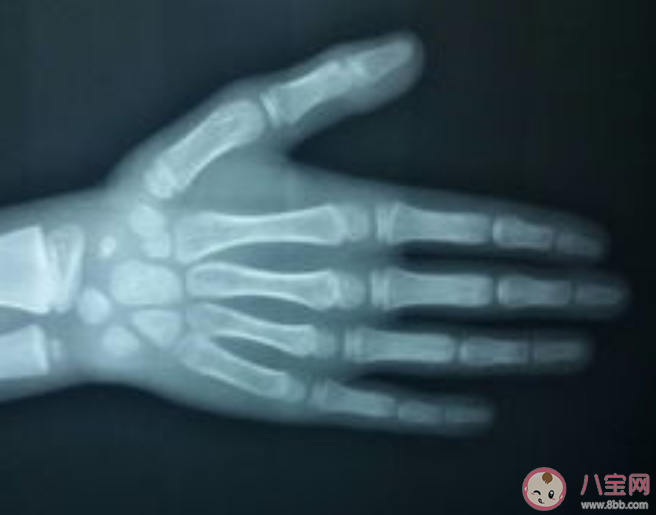

骨骼是反映骨骼生長情況與人體發育程度的重要指標。骨齡,從字面理解就是骨骼的年齡,其實就是兒童骨骼實際發育程度與標準發育程度比較的結果。骨齡是由X光來確定的,一般情況下會拍攝左手腕處,通過對手掌指骨、腕骨與橈尺骨下端骨化中心的發育情況進行觀察最終確定骨齡。